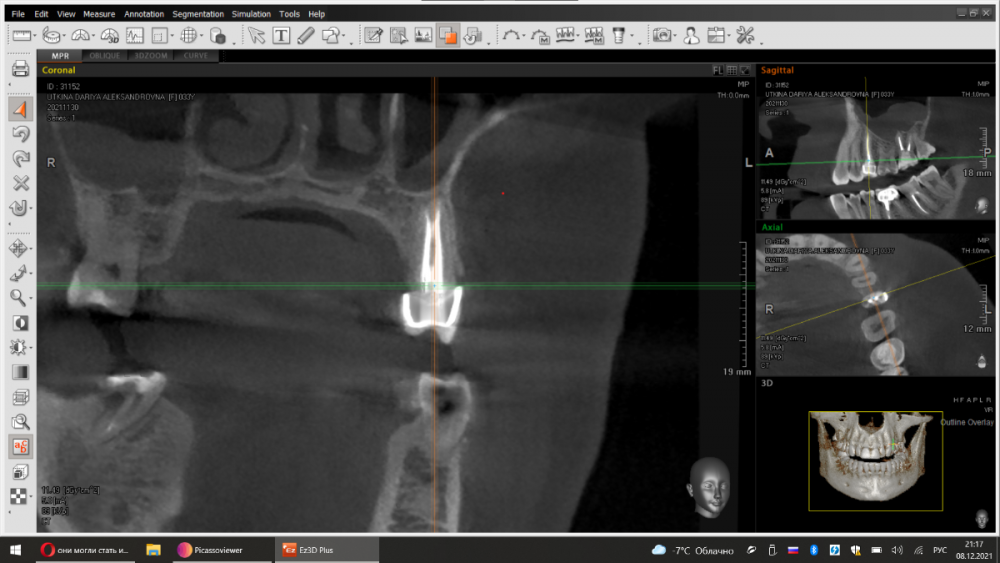

dentikl Опубликовано 7 декабря, 2021 Поделиться Опубликовано 7 декабря, 2021 Срезы кт через 6 месяцев терапии.Старый кальциевый протокол.Результат до постоянного пломбирования каналов. 3 Ссылка на комментарий

dentikl Опубликовано 7 декабря, 2021 Автор Поделиться Опубликовано 7 декабря, 2021 два клинических случая,смена кальция раз в три месяца,кт контроль.После значительного уменьшения дефектов следовало постоянное пломбирование каналов с последующей протетикой.Случай первый. 1,2 срез-до ,3,4- через 6 месяцев. Случай второй 5,6 срез-до,7,8-после. Ссылка на комментарий

Женька Опубликовано 8 декабря, 2021 Поделиться Опубликовано 8 декабря, 2021 @dentikl ну посмотрите как выглядят зубы, все светятся Также и импланты на КТ светятся. Ссылка на комментарий

dentikl Опубликовано 8 декабря, 2021 Автор Поделиться Опубликовано 8 декабря, 2021 на реконструкции лучше чем в проекциях можно оценить степень повреждения (и динамику). Ссылка на комментарий